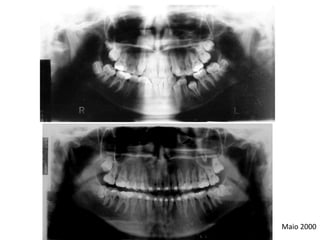

O documento descreve um caso de apinhamento dentário tratado sem extrações. O paciente apresentava asma, respiração bucal e língua hipotônica devido ao apinhamento. O tratamento envolveu remodelação dos dentes sem extrair nenhum, corrigindo o desvio de linha média.